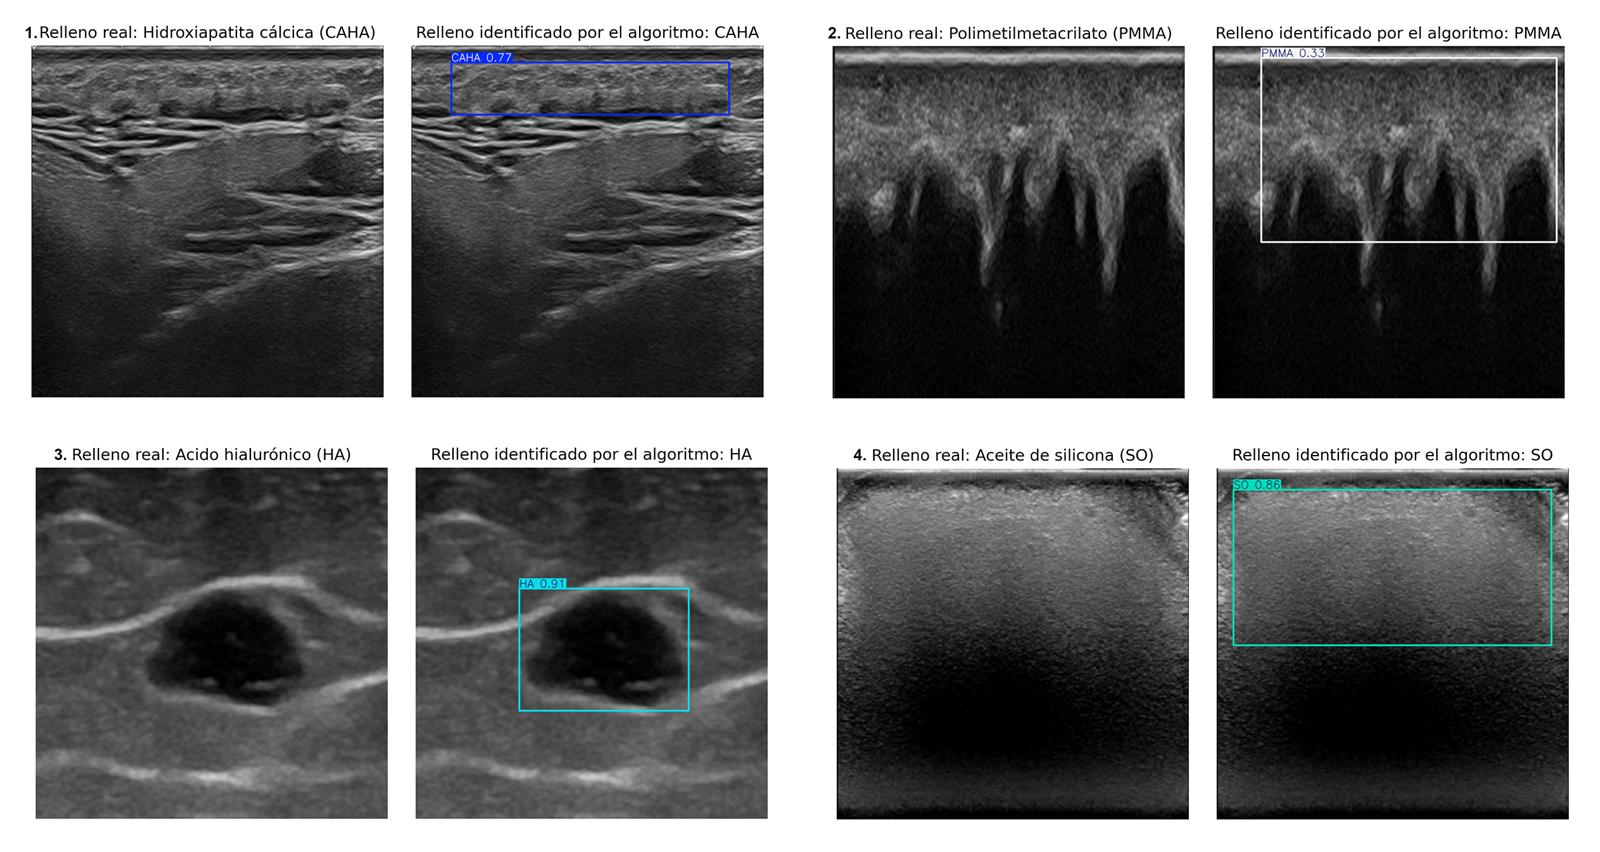

Un equipo internacional de investigadores de la Universidad de Granada (UGR) y la Universidad de Chile ha creado un sistema de inteligencia artificial que identifica automáticamente cuatro tipos de rellenos estéticos en imágenes ecográficas. El estudio, recientemente publicado en la revista Journal of Ultrasound in Medicine, promete agilizar el diagnóstico de complicaciones derivadas de estos tratamientos, mejorar la planificación clínica y facilitar una atención más eficaz incluso en centros con menos especialistas cualificados.

El nuevo algoritmo, basado en técnicas de aprendizaje profundo, ha sido desarrollado bajo la dirección de la doctora Ximena Worstman, de la Universidad de Chile, con la participación de Manuel Lozano y Francisco J. Rodríguez, del Departamento de Ciencias de la Computación e Inteligencia Artificial de la UGR. El sistema puede discriminar entre hidroxiapatita cálcica, ácido hialurónico, polimetilmetacrilato y aceite de silicona, cuatro de los rellenos más habituales.